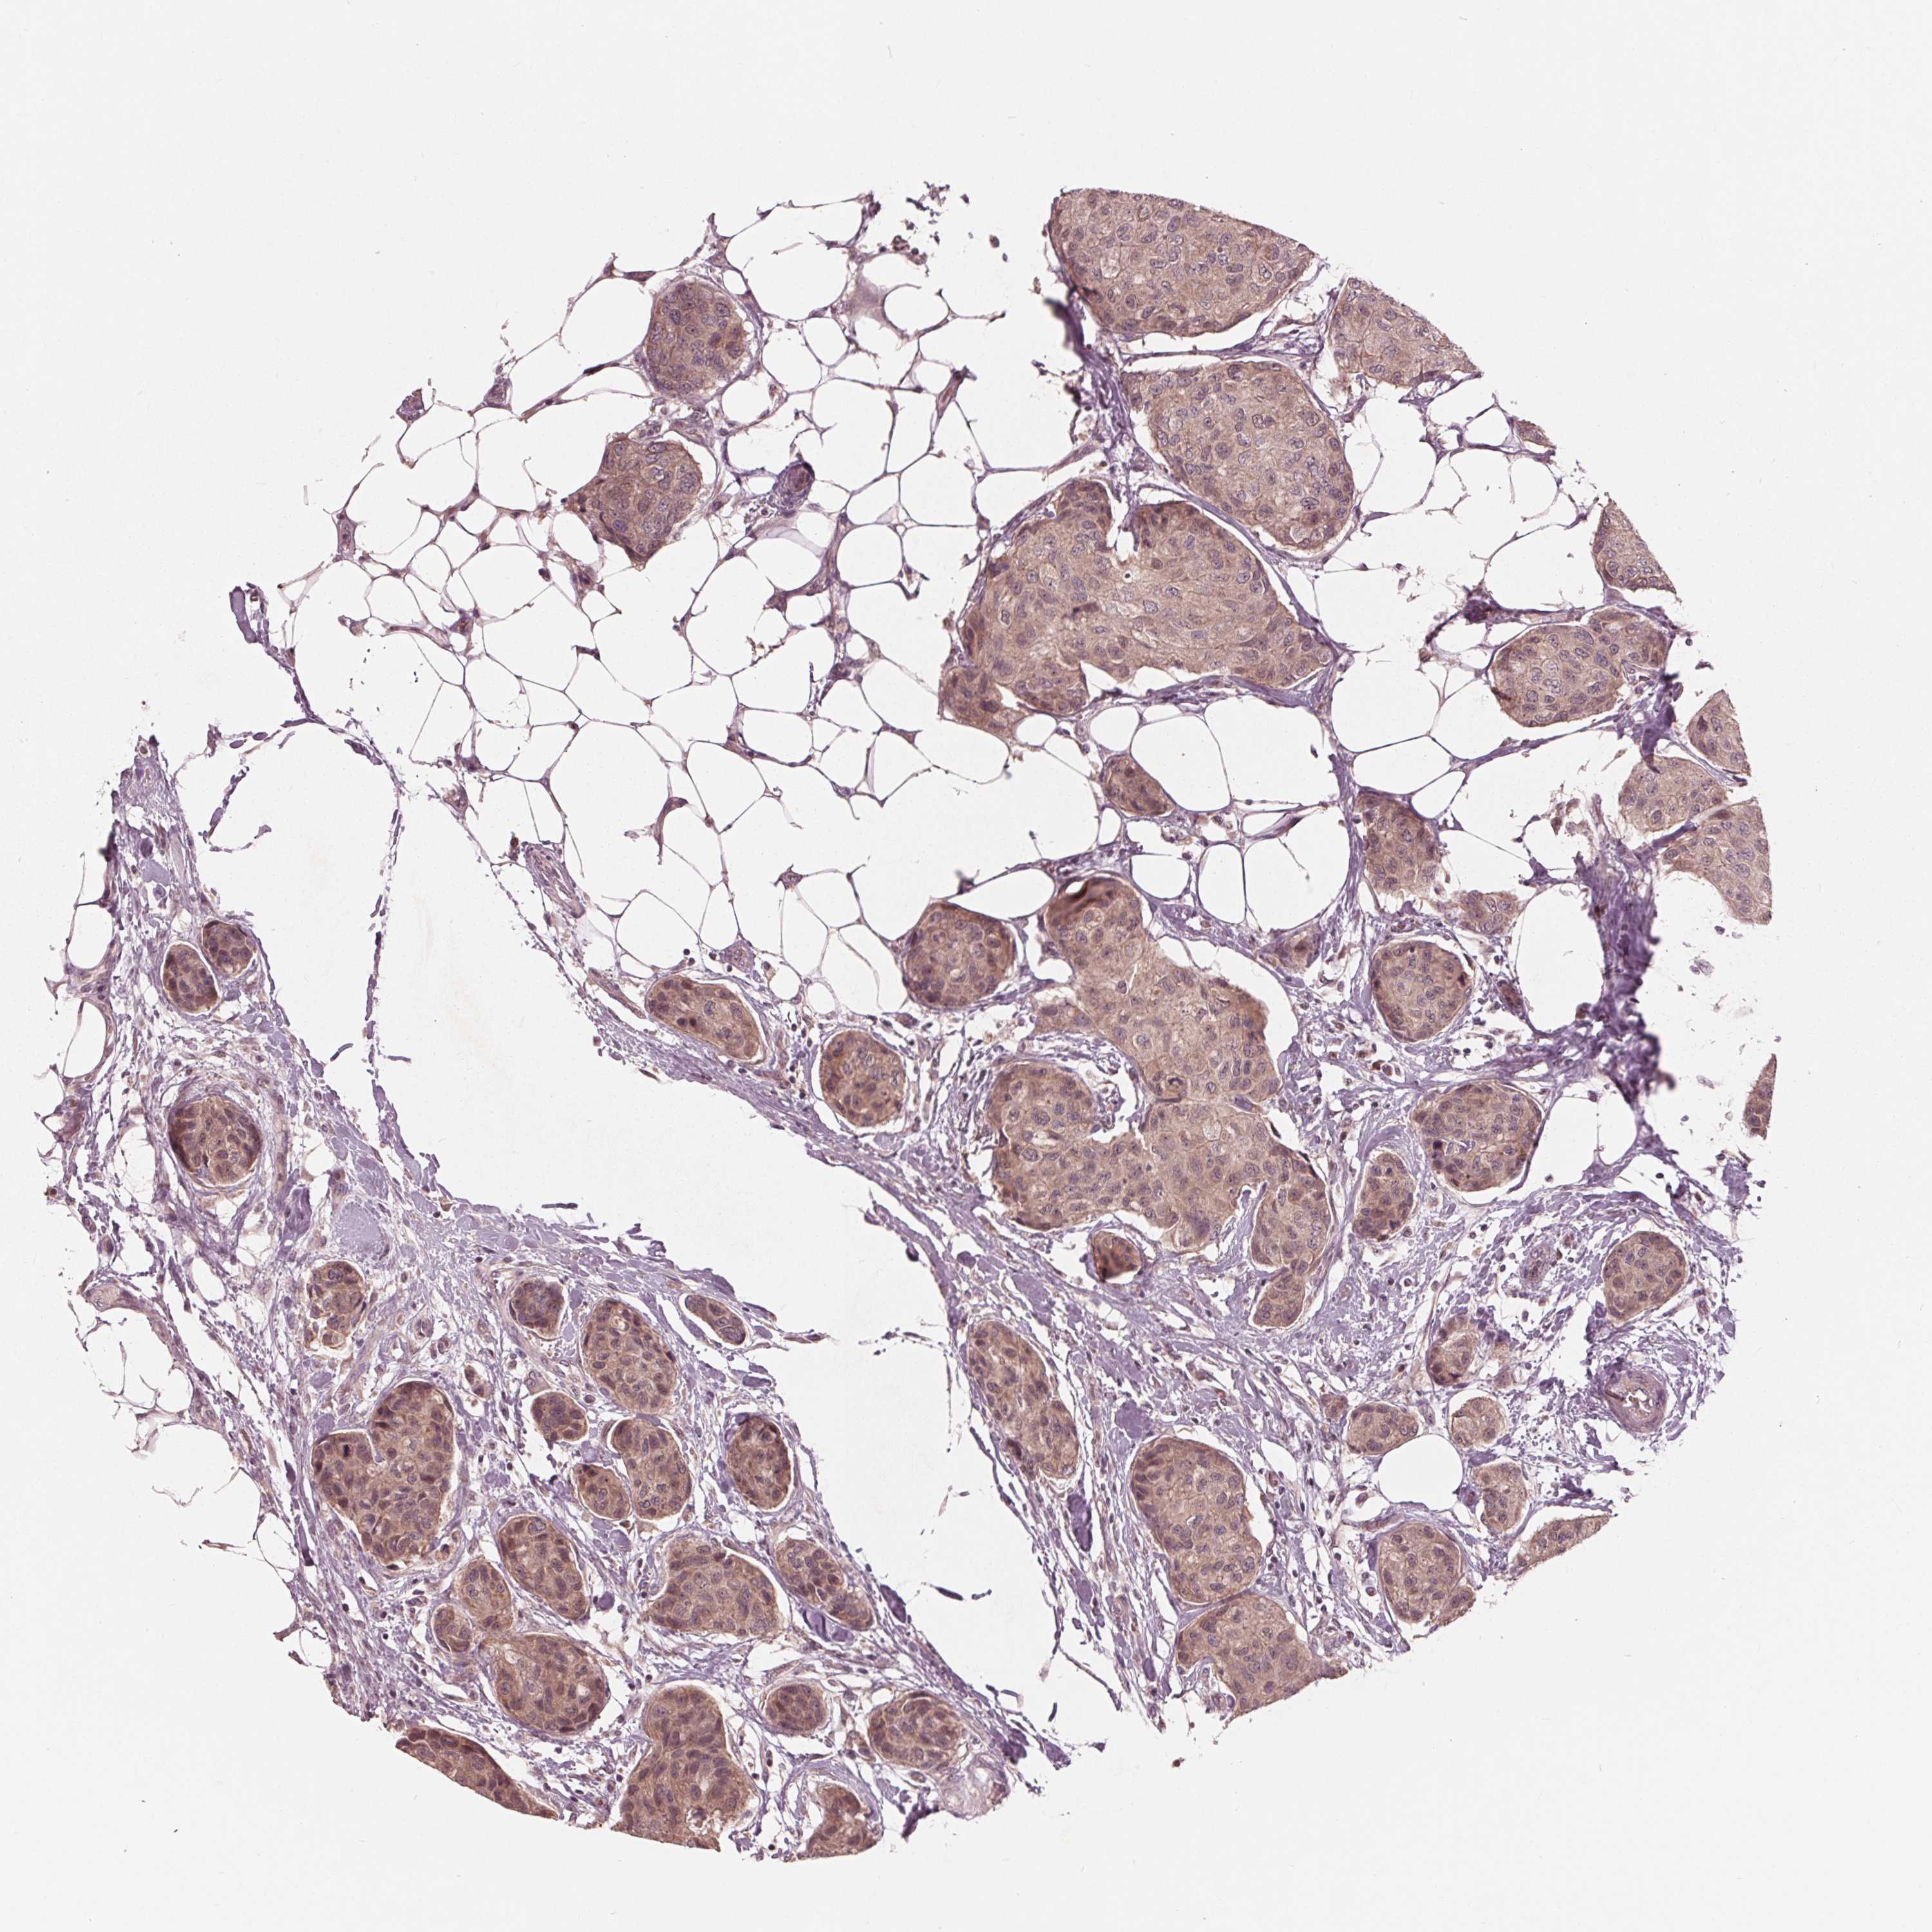

CANCER BREAST CANCER Show tissue menu

BRCA TCGA BRCA VALIDATION PROTEIN EXPRESSION

ANTIBODIES

AND

VALIDATION